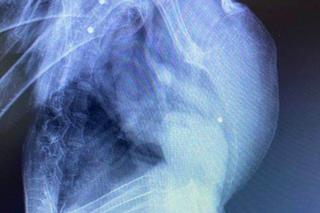

Przez bestialstwo człowieka znów ucierpiało zwierzę. Tym razem ofiarą bezmyślności i agresji padł bocian Roger, z którego ktoś zrobił sobie strzelnicę! Ptak trafił do Fundacji Ada w Przemyślu z czterema ranami od śrutu.

Dwie kule utknęły pod skrzydłami, dwie w płucach bociana.

- Jeden śrut, który utkwił najpłycej udało się wyciągnąć, co z pozostałymi, nie wiadomo. Najgorsze jest to, że bocian najprawdopodobniej przewrócił się, gdy ktoś do niego strzelił i wówczas złamał skrzydło. Uraz był tak poważny, że trzeba było amputować mały kawałek, ale ważny kawałek kości w skrzydle. Niestety to spowoduje, że  bocian już nigdy nie poleci- mówiła weterynarz Agnieszka Majchrowicz.

Postrzelonemu Bocianowi Rogerowi trzeba było amputować część skrzydła